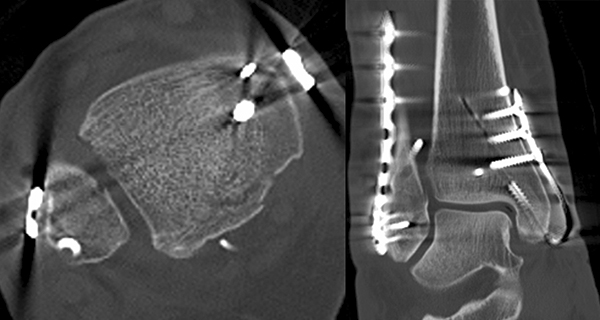

Liegt eine Fraktur des oberen Sprunggelenks vor, ist sowohl zur Entscheidung für ein konservatives oder operatives Vorgehen, als auch zur Operationsplanung, ein ausreichendes Verständnis der Fraktur und ihrer Morphologie notwendig. Insbesondere bei komplexen Verletzungen ist dafür die konventionelle Röntgenaufnahme in vielen Fällen nicht ausreichend. So konnten z.B. Black et al. zeigen, dass die operative Strategie zur Versorgung von OSG-Frakturen in 24% basierend auf einer zusätzlichen CT-Bildgebung relevant geändert wurden 7. Dies betraf die Lagerung, die Wahl des Zuganges und die Art der osteosynthetischen Versorgung. Besonders häufig änderte sich das Vorgehen bei Verletzungen des medialen (21%) und des posterioren Malleolus (15%). Darüber hinaus führten dislozierte (dislozierte Frakturen 31% vs. nicht-dislozierte Frakturen 20%) oder komplexe Frakturen (Trimalleolar-Frakturen 29% vs. Unimalleolar-Frakturen 10%) besonders häufig zu relevanten Änderungen des operativen Vorgehens. Die Computertomographie ist daher, insbesondere bei Bi- und Trimalleolar-Frakturen, essentiell für das Verständnis der Fraktur und somit für die Planung und Durchführung der Operation. In Abbildung 4 und 5 sind exemplarisch ein Röntgen- und ein CT Befund gegenübergestellt.